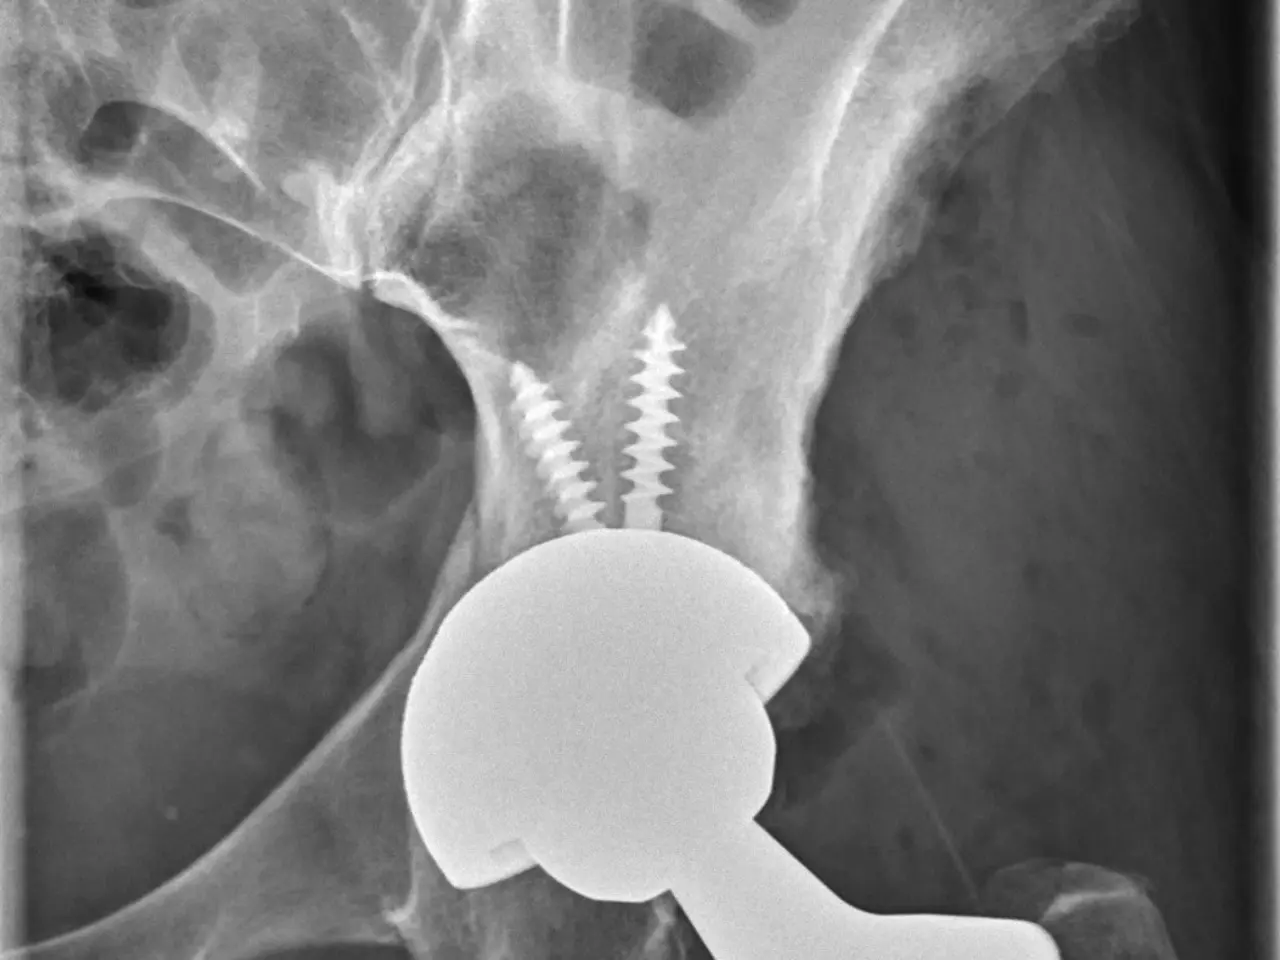

The image shows an x-ray of a hip joint with a screw inserted into it.